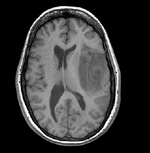

Slicer Registration Library Case #9: fMRI to structural MRI

This shows registration of an fMRI baseline scan to a structural reference T1. The fMRI suffers from low SNR and bad distortions we seek to correct. Approach: we first compute a rigid alignment of the fMRI to the T1. We then expand this to a nonrigid transform, which we constrain either by explicit limits on the absolute deformation amount or via a mask. Constraints are necessary because the skull present in the T1 would otherwise negatively affect the registration result.